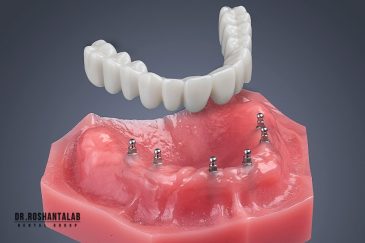

🔸 کاشت ایمپلنت دندان بدون درد

🔸کاشت ایمپلنت فلپ لس یا بدون جراحی و بدون بخیه زیر سه دقیقه

🔸 کاشت دندان یک روزه ( کشیدن و کاشت همزمان )

🔸 ایمپلنت دیجیتال و ساخت روکش دیجیتال

تجربه کاشت دندان دیجیتال و بدون درد در ۳ دقیقه! استفاده از برترین برندها زیر نظر جراح، با هزینه مناسب و خدمات کامل از کاشت دندان تا روکشارتودنسی دندان